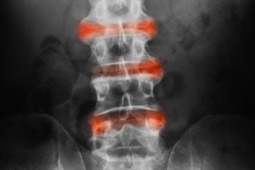

Ocena ruchomości kręgosłupa i rozszerzalności klatki piersiowej stanowią jedne z podstawowych narzędzi służących ocenie progresji zmian osiowych w przebiegu zesztywniającego zapalenia stawów kręgosłupa (ZZSK).

Wyniki analizy oceniającej zmiany w zakresie parametrów oceny ruchomości kręgosłupa wykazują, że najczęściej obserwowanymi nieprawidłowościami są (w kolejności malejącej częstości występowania): zgięcie boczne kręgosłupa - LSF (ang. lateral spinal flexion, ograniczenie ruchomości odcinka lędźwiowego kręgosłupa w płaszczyźnie czołowej), zmodyfikowany test Schobera, odległość tragus – ściana, rotacja odcinka szyjnego kręgosłupa, odległość międzykostkowa i rozszerzalność klatki piersiowej. Obserwowana kolejność zmian była stała na przestrzeni czasu i niezależna od płci, czasu trwania objawów oraz obecności zmian radiologicznych – syndesmofitów. Przy ocenie tylko jednego parametru oceny ruchomości kręgosłupa – LSF, ryzyko „przeoczenia” upośledzenia zakresu ruchomości kręgosłupa wynosiło 14%, przy ocenie dwóch parametrów (LSF + zmodyfikowany test Schobera) już tylko 9%. Przy ocenie co najmniej jednego wskaźnika u 86% badanych stwierdzono nieprawidłowości dotyczące LSF.

W przebiegu ZZSK ograniczenie ruchomości kręgosłupa dotyczy w kolejności odcinka lędźwiowego, piersiowego i szyjnego. Biorąc pod uwagę uzyskane wyniki, LSF i zmodyfikowany test Schobera mogą stanowić narzędzia szybkiej, przesiewowej oceny wpływu choroby na upośledzenie ruchomości kręgosłupa. Jednoczesną ocenę LFS i zmodyfikowanego testu Schobera należy traktować wówczas jako minimum niezbędne do wykazania zaburzeń ruchomości kręgosłupa w przebiegu ZZSK.